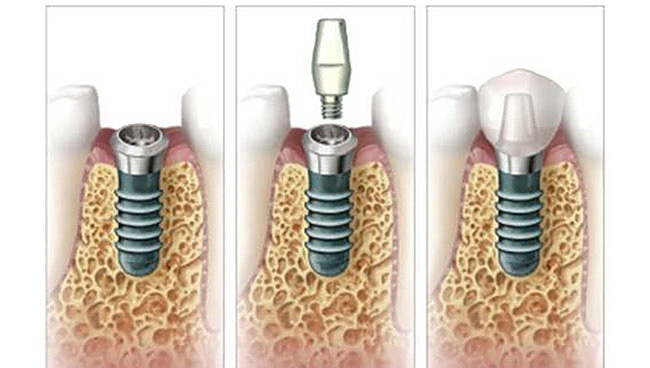

Faze ugradnje implantata

- Implantati se hirurški ugrađuju u kost. Postupak je brzo gotov i bezbolan, budući da se izvodi pod lokalnom anestezijom. Nakon ugradnje implant srasta sa kosti - “osteointegracija“ , što obično traje 2 do 6 meseci.

- Nakon ovog perioda na implant se postavlja nadgradnja (suprastruktura) na koju ide protetska krunica ili neko drugo protetsko resenje u zavisnosti od plana terapija.